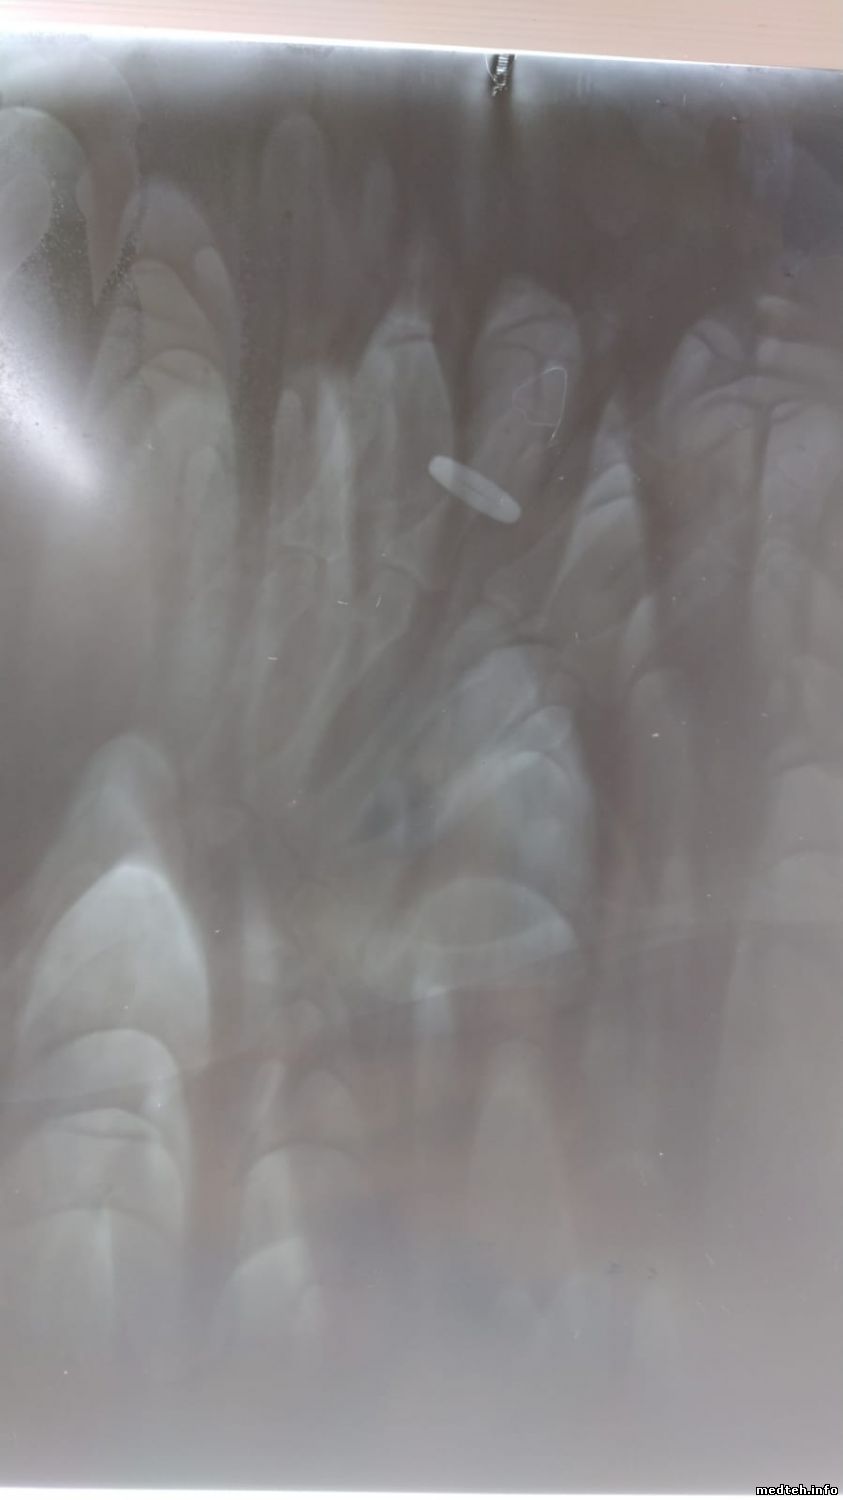

Всё сделал. Заработал.

И теперь вопрос: может кто подскажет откуда такие артефакты на снимке?

6518924.jpg (53.6 Kb)

Такое чувство, что плёнку только в проявителе подержали и вынули на свет.

terbunyДата: Среда, 01.Мар.2023, 12:06 | Сообщение # 79

Похоже на то, что на этой плёнке сделали много экспозиций.

Разобрались. Это разводы от проявителя. Получается нужно плёнку постоянно двигать, пока идёт проявка.